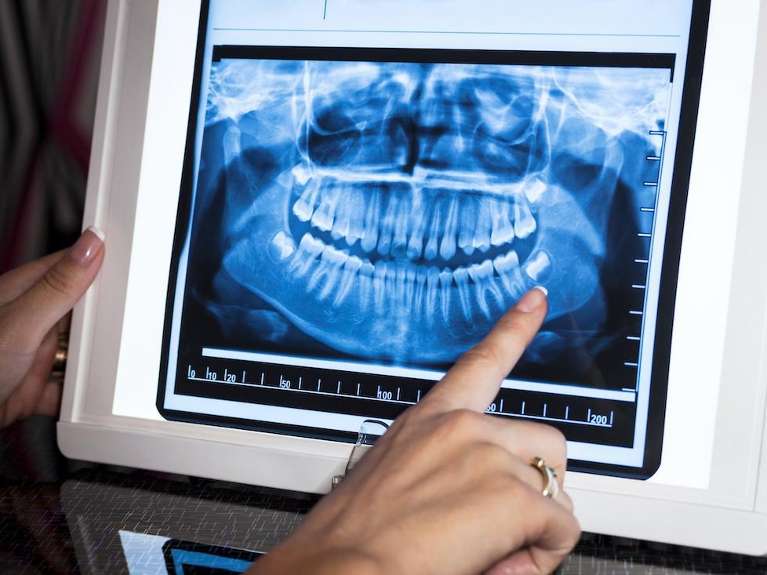

Panoramic X-Rays

A panoramic X-ray provides a full view of your teeth and jawbone with one image. These types of X-rays help us plan dental implant placement, orthodontic treatment, and wisdom tooth extractions.